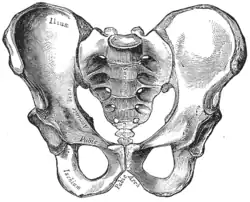

| Comparação entre uma pelve androide (esquerda) e uma ginecoide (direita). | |

Os serviços obstétricos tradicionais dependiam fortemente da pelvimetria na condução do parto para decidir se o parto vaginal natural ou operatório era possível, ou se e quando recorrer a uma cesariana.[9] Mulheres cujas pelves eram consideradas pequenas recebiam cesarianas em vez de parirem naturalmente.

A obstetrícia tradicional caracterizou quatro tipos de pelves:

- Ginecoide: forma ideal, com abertura superior arredondada a levemente oval (entrada obstétrica ligeiramente menos transversa).

- Androide: abertura triangular, espinhas isquiáticas proeminentes, arco púbico mais angulado.

- Antropoide: o maior diâmetro transverso é menor que o diâmetro obstétrico ântero-posterior.

- Platilipeloide: abertura superior achatada, com diâmetro obstétrico reduzido.